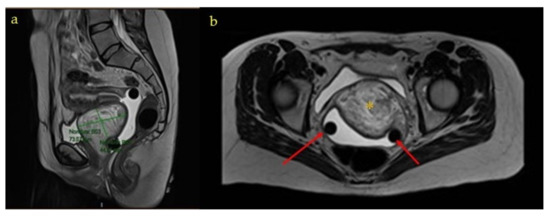

Genital Prolapse in Pregnant Woman as a Presentation of Aggressive Angiomyxoma: Case Report and Literature Review

by María Pilar Espejo-Reina, Miriam Prieto-Moreno, Marina De-Miguel-Blanc, Daniela María Pérez-Martínez, Jesús Salvador Jiménez-López and Susana Monís-Rodríguez

Medicina 2022, 58(1), 107; https://doi.org/10.3390/medicina58010107 - 10 Jan 2022

Background: Aggressive angiomyxoma is a rare entity within mesenchymal cell neoplasms, especially in pregnant women. Its main characteristic is the ability to infiltrate neighboring structures and to recur. Case Presentation: We present the case of a pregnant woman who debuted with a genital prolapse in the second trimester of pregnancy. She was diagnosed with bilateral ovarian teratomas and a pelvic mass of which the diagnosis could not be established until delivery. The route of delivery used was cesarean section since the genital prolapse behaved as a previous tumor. After the puerperium, the patient was referred for consultation to complete the study of the mass. The extension study was carried out with a negative result. The patient underwent surgery for tumor exeresis. Hormonal treatment was not administered according to the patient’s preferences. Conclusions: Aggressive angiomyxoma is a benign neoplasm that should be considered in the differential diagnosis of pelvic tumors in women. In pregnant women, the vaginal route of delivery is not contraindicated as long as the tumor does not obstruct the birth canal. The definitive treatment is surgery, preferably performed in a second stage after delivery. Full article

Figure 1